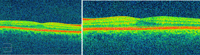

En el fondo de ojo se aprecia alteración del EPR bilateral, sin edema macular (Figura 2 y Figura 3).

Figura 2. Retinografía derecha e izquierda: alteraciones del epitelio pigmentario retiniano.

Figura 3. OCT derecho e izquierdo respectivamente, ambos sin alteraciones.

La agudeza visual es de 0,15 en ojo derecho (OD) y de 0,2 en OI. En el fondo de ojo derecho se aprecia retinopatía diabética no proliferativa moderada, en OI retinopatía diabética no proliferativa moderada con edema macular, infiltrado vítreo central, la Tomografía de Coherencia Óptica (OCT) es normal en OD y presenta edema macular de 518 micras en OI. En OCT realizada dos meses antes en un control, no existía edema macular en OI.